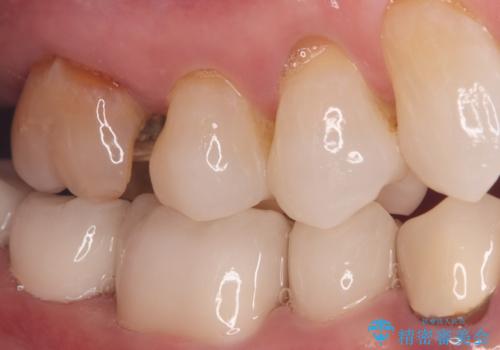

オールセラミッククラウンによる修復: 根管内が清潔に封鎖されたことを確認した後、土台を立てて歯の形を整えました。最終的な被せ物には、金属を一切使用しないオールセラミッククラウンを選択。天然歯のような透明感を再現し、高い適合性によって再び虫歯になるリスクを抑えています。

今回の治療により、詰め物が取れた根本的な原因が解消され、見た目も美しく、長持ちする奥歯を再建することができました。